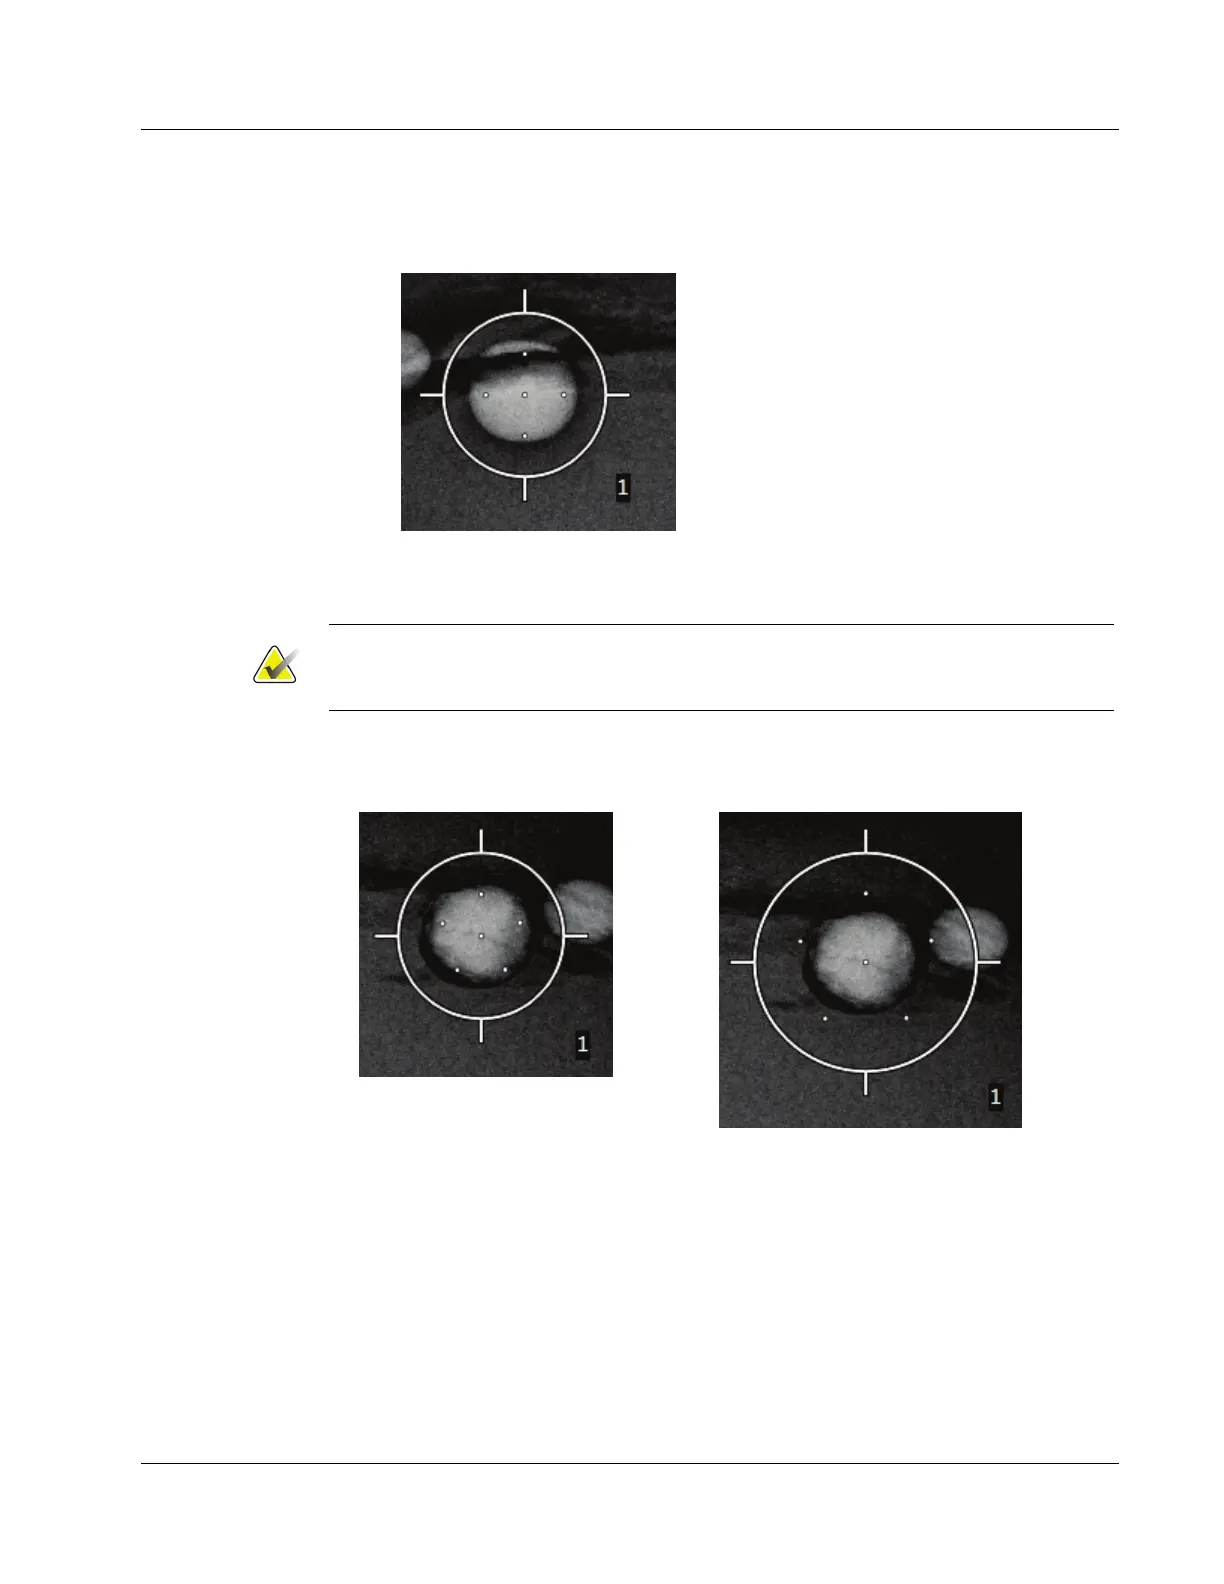

5. Select the number of offset target points (three, four, or five) you require around the

center target point.

Figure 56: Four Offset Target Points

Established Around Center Target Point

Keep in mind that the center target point is included in the total target points. Choosing

a "four" offset, for example, generates a total of five target points.

6. Select how far the offset target points are automatically generated from the center

target point - 2 mm, 3 mm (the default), 4 mm, or 5 mm.

Figure 57: 3 mm Spacing of Offset Points

Figure 58: 5 mm Spacing of Offset Points